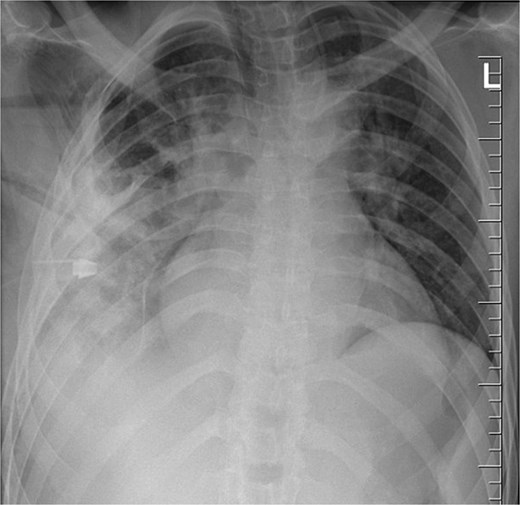

The patient was monitored in the Surgical Intensive Care Unit for 24 hours before being transferred to a general ward. Seven days post-op, a chest X-ray showed a chest tube in situ and lung opacification, consistent with the pleural collection and expected changes (Fig. 5). The chest tube was removed on day eight when the drainage was less than 100 ml in 24 hrs., and the patient was discharged on postoperative day 10. His follow-up appointments on day 14 and week six were uneventful.

Chest radiograph post-operatively, demonstrating a chest tube in situ, residual lung opacification, and expected post-surgical changes following removal of a retained thoracic foreign body (knife).